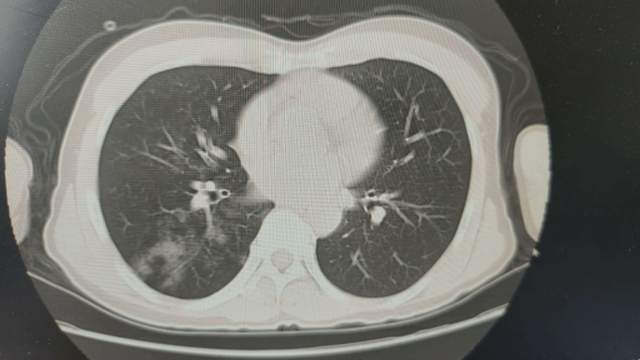

患者到院后,急诊科为患者予以垂体后叶素持续泵入止血,并联系肺病科会诊,同时完善相关血液检验及急诊支气管动脉CTA检查,CT显示右肺多发斑片状高密度影,考虑为肺部支气管扩张导致右肺出血。

CT显示右肺多发斑片状高密度影